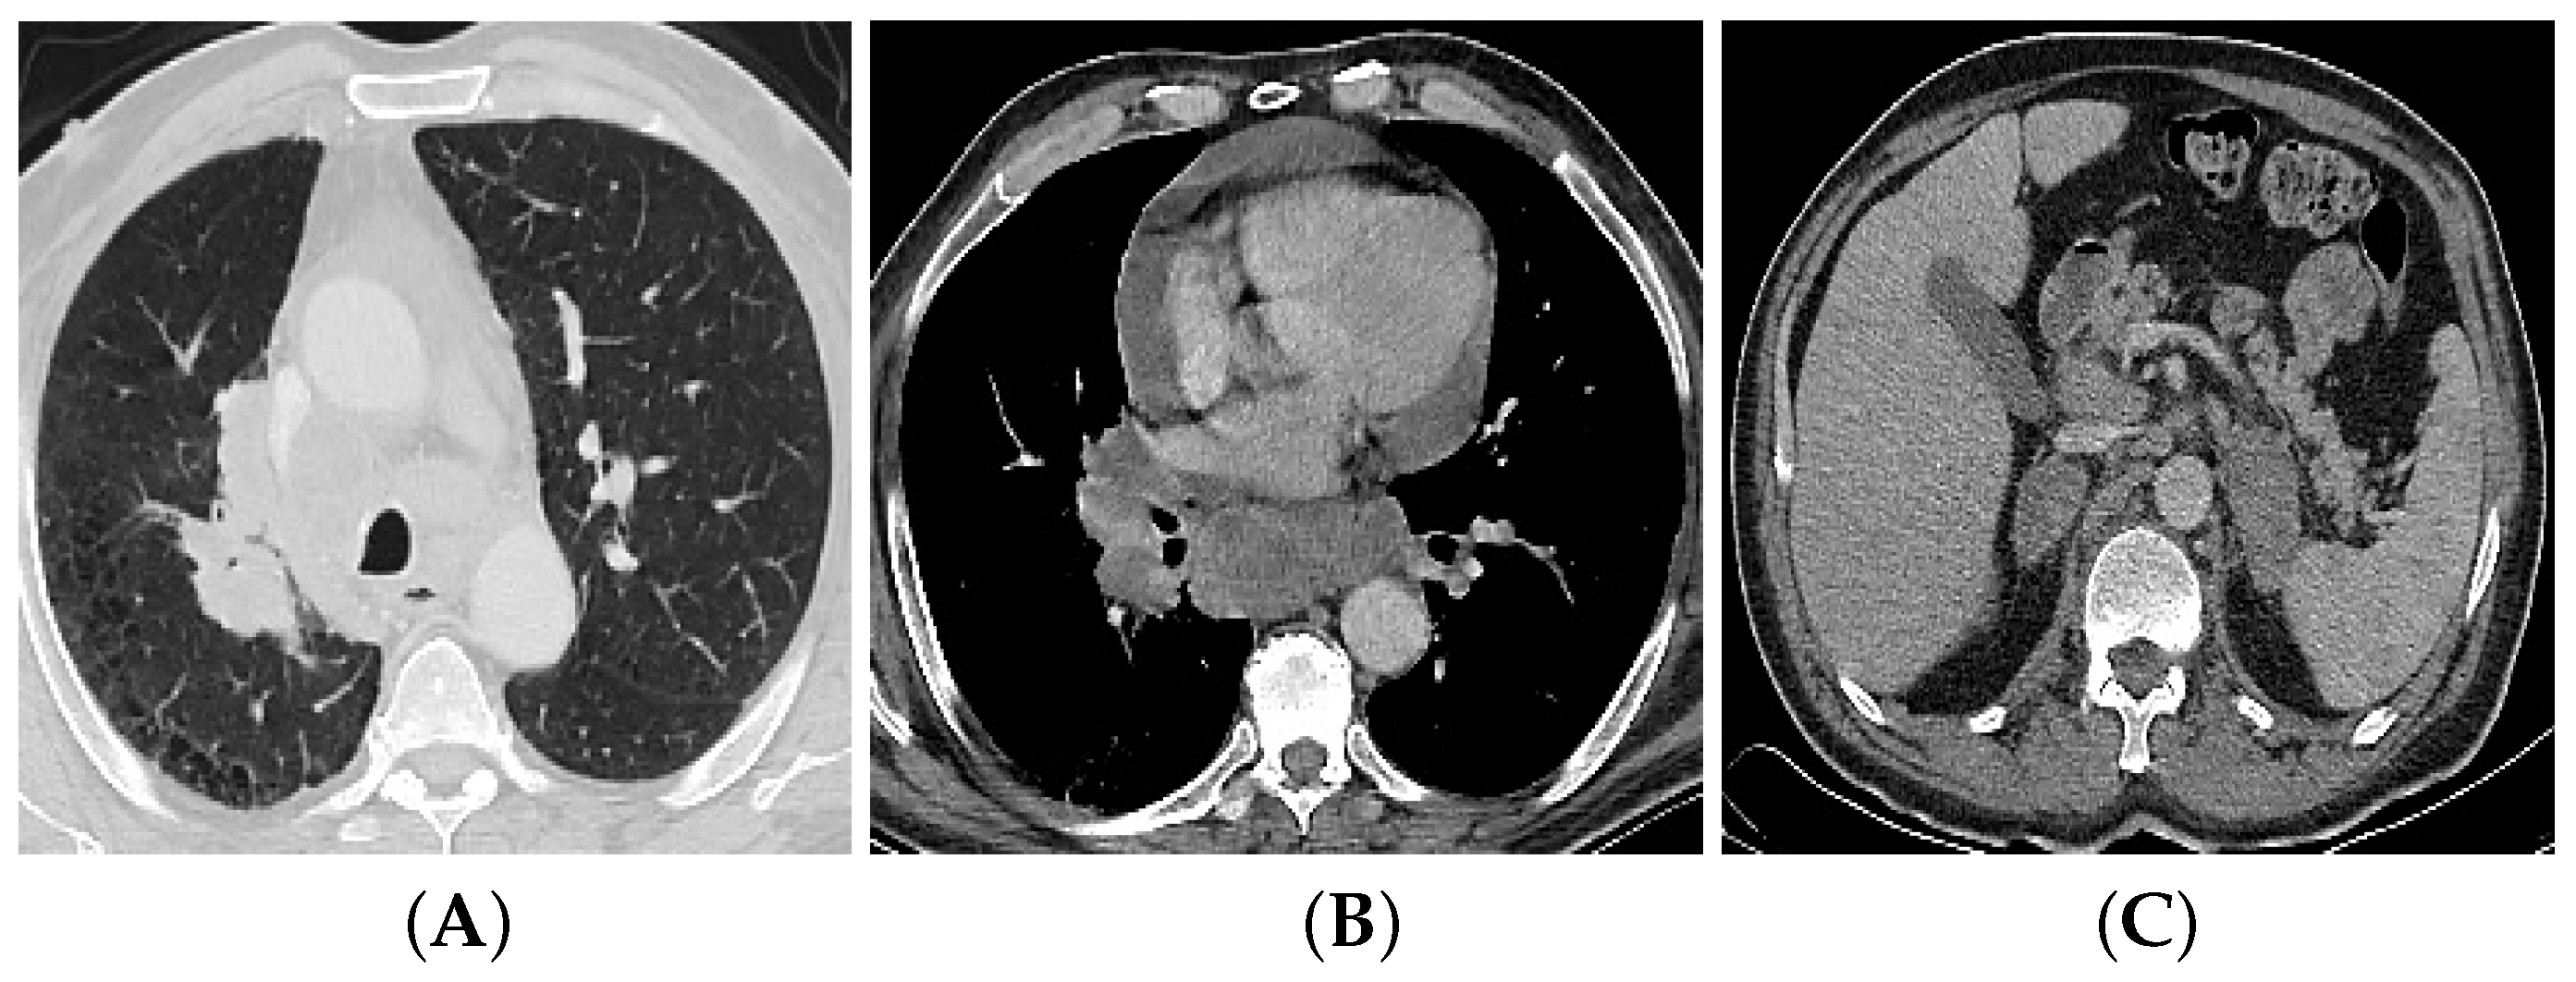

3.2. Multi-Detector Computed Tomography (CT)

4.1. T (Tumor) Descriptor

4.2. N (Nodal) Descriptor

4.3. M (Metastasis) Descriptor